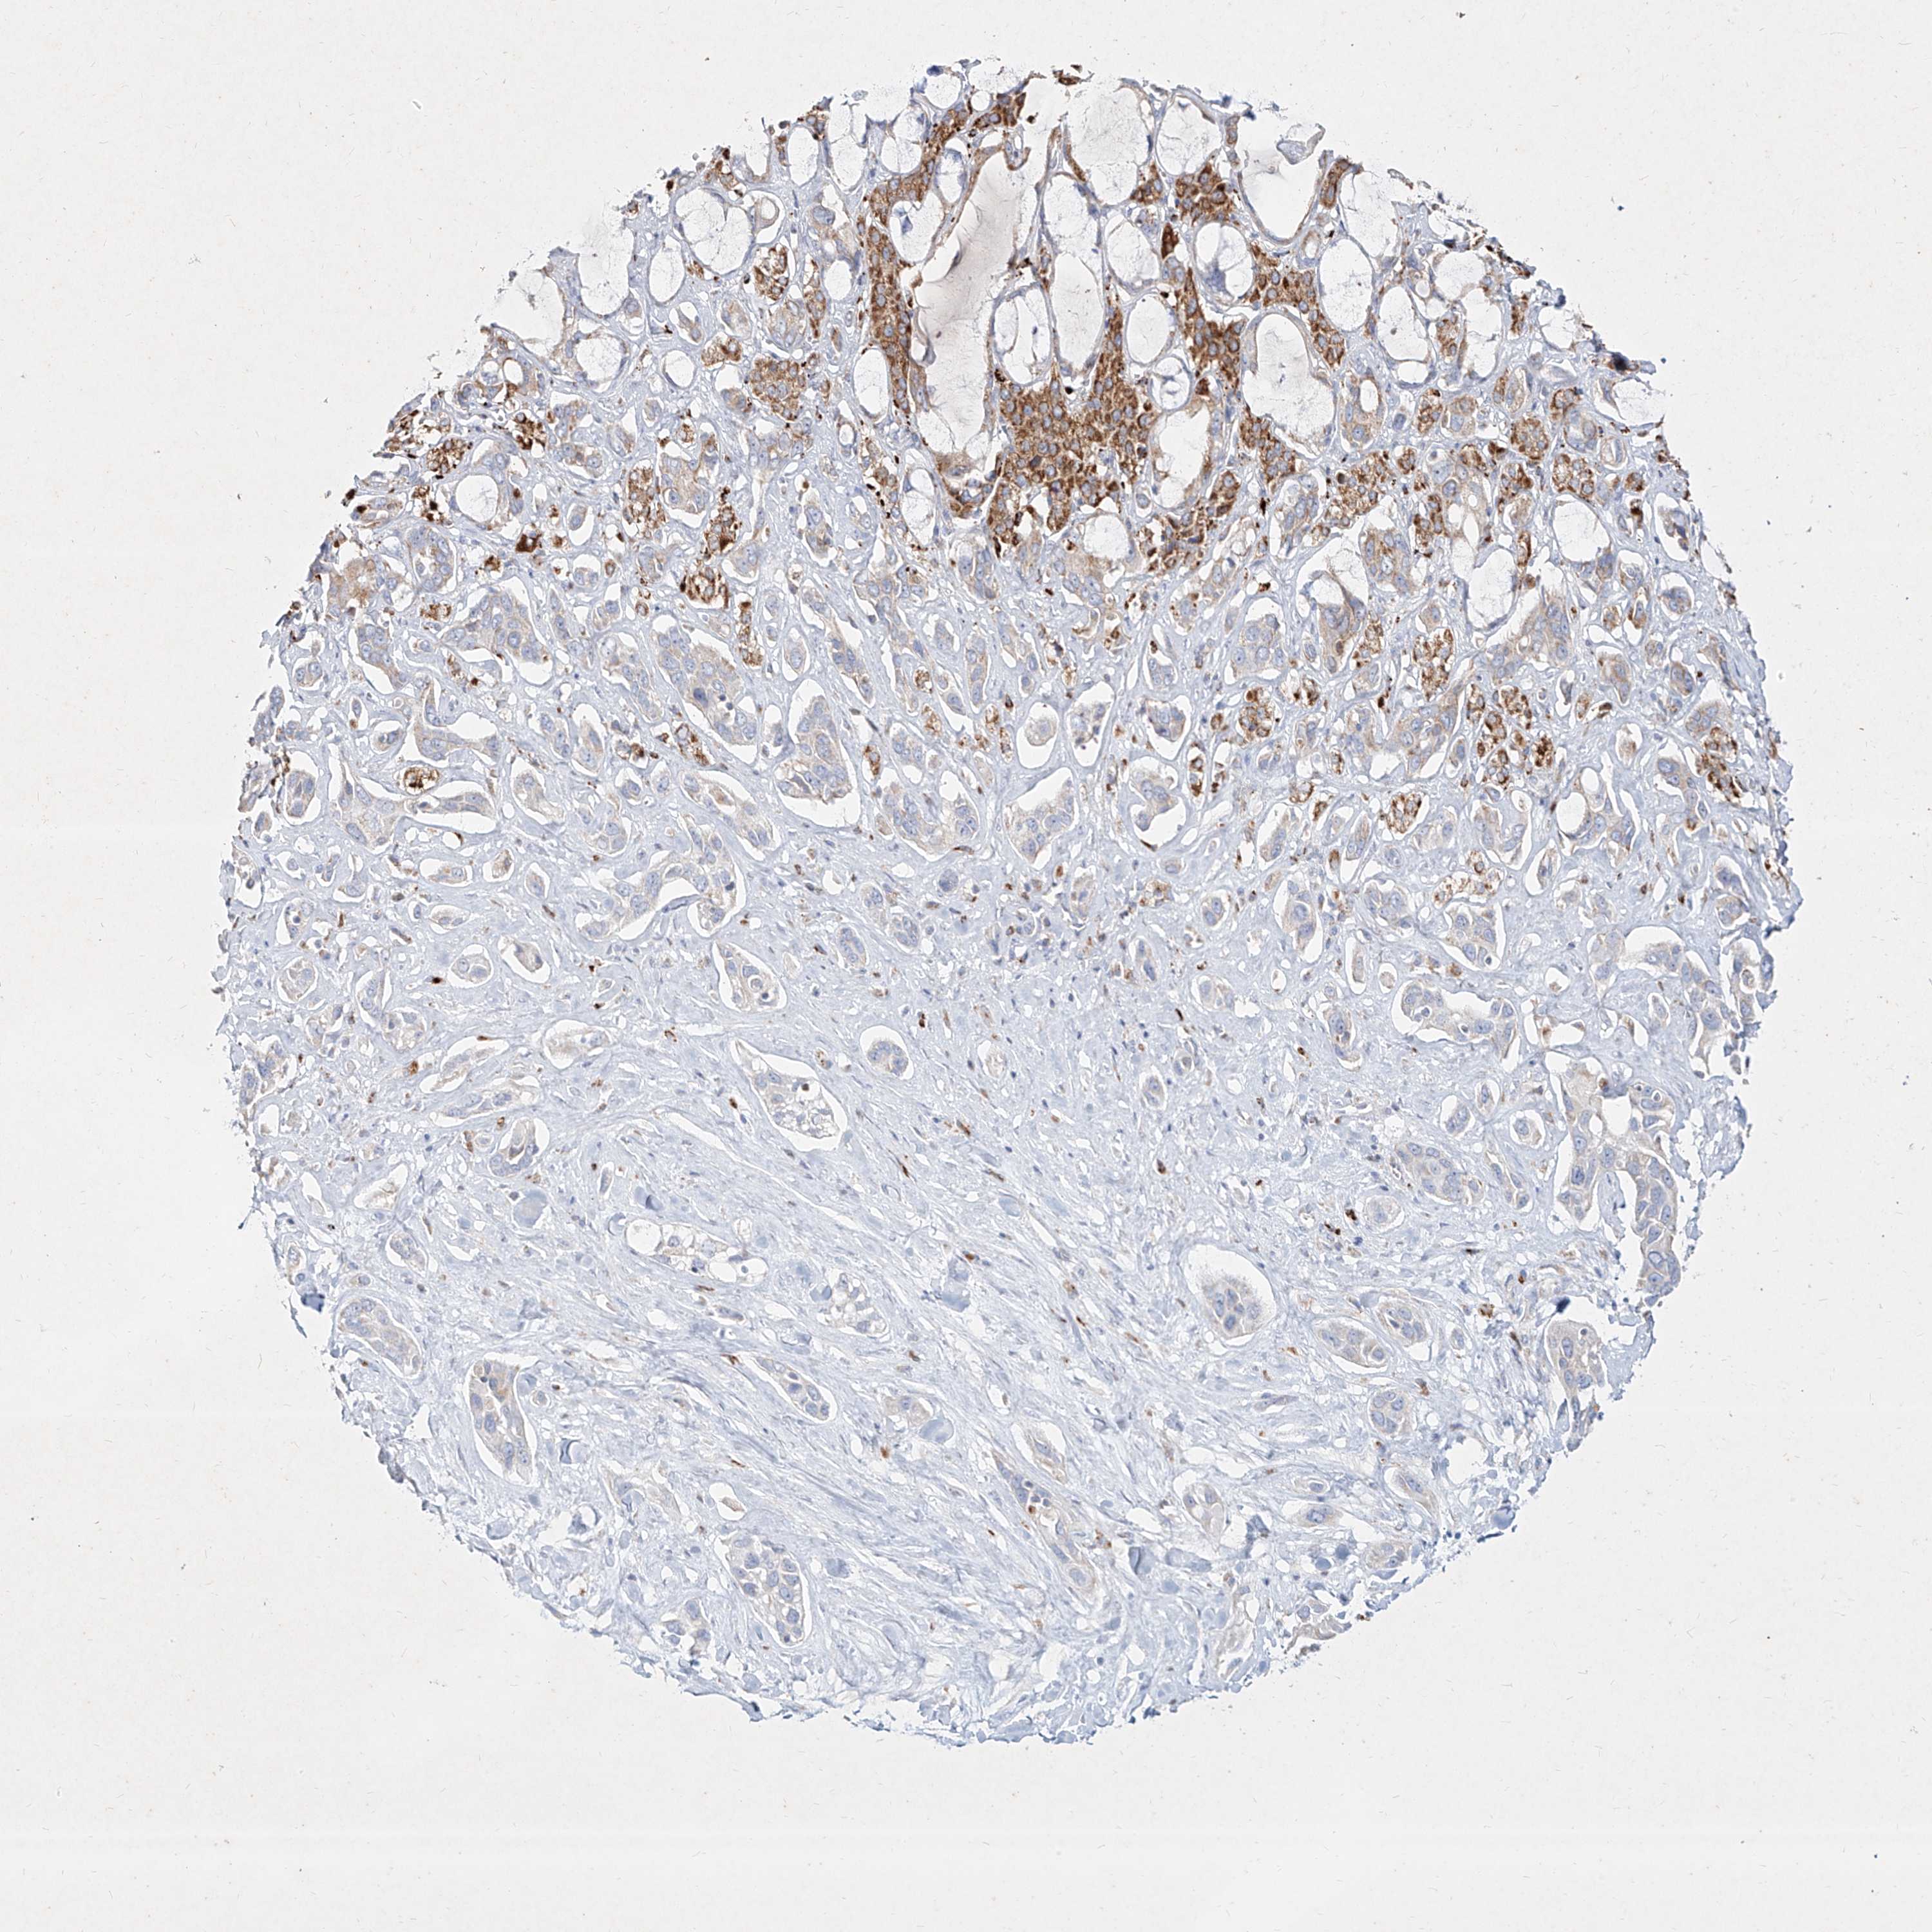

PANCREATIC CANCER - Protein expressioni

A mouse-over function shows sample information and annotation data. Click on an image to view it in a full screen mode. Samples can be filtered based on level of antibody staining by selecting one or several of the following categories: high, medium, low and not detected. The assay and annotation is described here.

Note that samples used for immunohistochemistry by the Human Protein Atlas do not correspond to samples in the TCGA dataset.

Antibody stainingi

Antibody staining in the annotated cell types in the current human tissue is reported as not detected, low, medium, or high, based on conventional immunohistochemistry profiling in selected tissues. This score is based on the combination of the staining intensity and fraction of stained cells.

Each image is clickable and will lead to virtual microscopy that enables deeper exploration of all samples and also displays staining intensity scores, fraction scores and subcellular localization as well as patient and tissue information for each sample.

Antibody HPA031550

Antibody HPA031551

Antibody HPA031552

Staining

High

Medium

Low

Not detected

Intensity

Strong

Moderate

Weak

Negative

Quantity

>75%

75%-25%

<25%

None

Location

Nuclear

Cytoplasmic/membranous

Cytoplasmic/membranous,nuclear

Adenocarcinoma, NOS